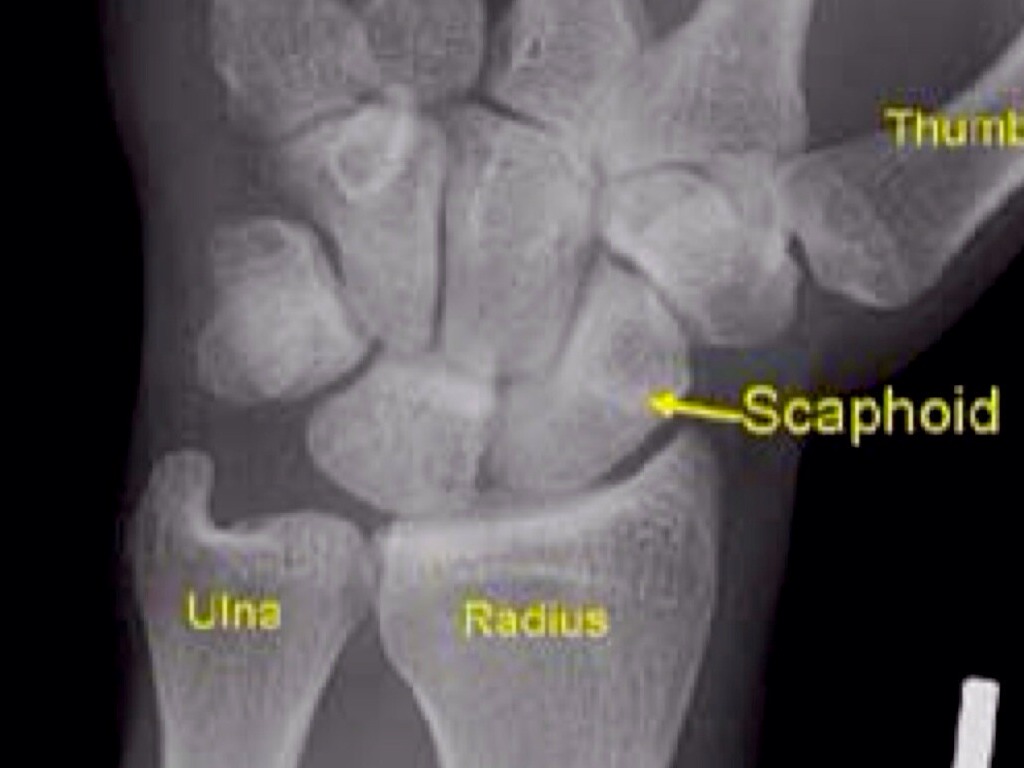

BASIC SKILLS IN ANATOMY, BIOLOGY,PHYSICS, AND MATH